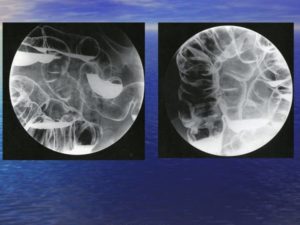

Гистеросальпингография – рентгенологическое исследование с использованием контрастных веществ, целью которого является определение проходимости полости матки и маточных (фаллопиевых) труб. Она позволяет выявить анатомические изменения в полости матки, спаечный процесс в малом тазу.

Исследование проводится при участии как врача рентгенолога, так и врача акушера – гинеколога, который вводит контрастное вещество в полость матки, после чего проводится рентгенологическое исследование.

В современной медицине общепринято, что проведение гистеросальпингографии показано на 9-11 и 17-19 дни менструального цикла, причем пациентке рекомендуется предохраняться от беременности в течение месяца до проведения обследования.

Гистеросальпингографию проводят теми же препаратами, что и экскреторную урографию – «Омнипак» и «Ультравист» (реже «Верографин» и «Урографин»). Возможно проведение исследования с помощью жирорастворимых контрастных веществ, однако это происходит значительно реже.

- Гистеросальпингография. Непроходимость маточной трубы. Женское бесплодие Пациентка 1982 г.р. наблюдается у врача-акушера гинеколога по поводу бесплодия. Менструация с 13 лет, по 5-6 дней, цикл – 28 дней. Роды – не было, аборты – нет, самопроизвольные аборты – нет. Наследственные заболевания отрицает. Подробнее …